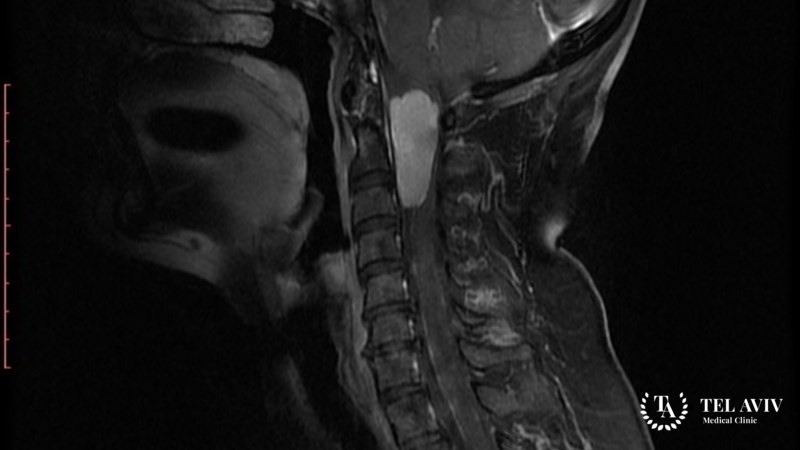

Менингиома увеличивается в размерах медленно, что становится причиной отсутствия первичной симптоматики. Человек не ощущает дискомфорта, не догадывается о наличии опухоли. Определяется заболевание компьютерной или магнитно-резонансной томографией. В большинстве случаев человек приходит на обследование по другим причинам. Менингиома обнаруживается случайно.

Для диагностики заболевания рекомендует провести компьютерную, магнитно-резонансную томографию на базе контрастного вещества. С помощью визуализации специалист получает информацию о взаимодействии новообразования и окружающих тканей, оценивает сосудистую системы. Томография выявляет костные патологии, онкологические, злокачественные опухоли, доброкачественные образования на любой стадии.